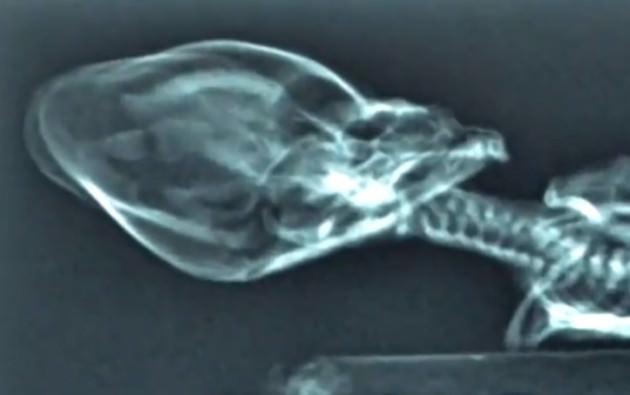

Küçük uzaylının DNA'sı çözüldü

Huffington Post’un haberine göre, Nolan şu açıklamada bulundu: “Kesin olarak söyleyebileceğim, bunun bir maymun olmadığı. Bu varlık bir insan. Şempanzeden çok insana daha yakın.